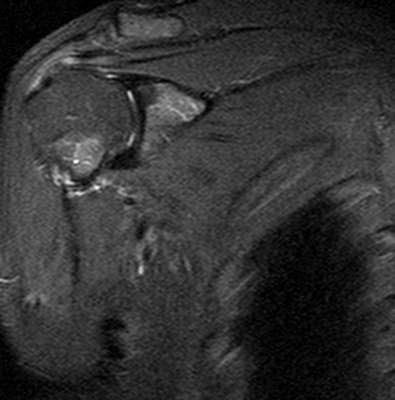

Явление магнитно-ядерного резонанса позволяет получить послойные изображения исследуемой зоны (срезы). По результатам МР-сканирования сложно выявить костные или сосудистые патологии, однако можно детально рассмотреть мягкие ткани и обнаружить следующие повреждения:

- поражения стабилизаторов плечевого сустава (губ, капсул, связок и т.п.);

- растяжения и разрывы мышц (двуглавой, трапециевидной, дельтовидной, ромбовидной и др.);

- перелом Хилла-Сакса (изменение формы наружной части головки плечевой кости);

- разрыв сухожилий ротаторной манжеты;

- (не)полные вывихи плечевой кости;

- артроз (деструктивно-дистрофические процессы);

- сращение суставных поверхностей сочленения;

- артрит (воспалительные процессы инфекционной, аутоиммунной или иной природы в сочленении);

- патологические характеристики (наличие крови, гноя) и изменение объема синовиальной жидкости;

- воспаление суставной сумки, мышц;

- остеохондропатии (нарушения трофики костей и хрящей, которые приводят к их некрозу);

- гнойные процессы (абсцесс, флегмона, остеомиелит);

- аномалии развития;

- нейропатии, поражения плечевого сплетения;

- дистрофию сухожилий;

- склеро- или некротические изменения элементов сочленения;

- новообразования.

Нативное МРТ досконально отражает анатомию плечевого сустава. Исследование с контрастированием позволяет выявить мельчайшие очаги воспаления, опухоли и нарушения кровообращения.